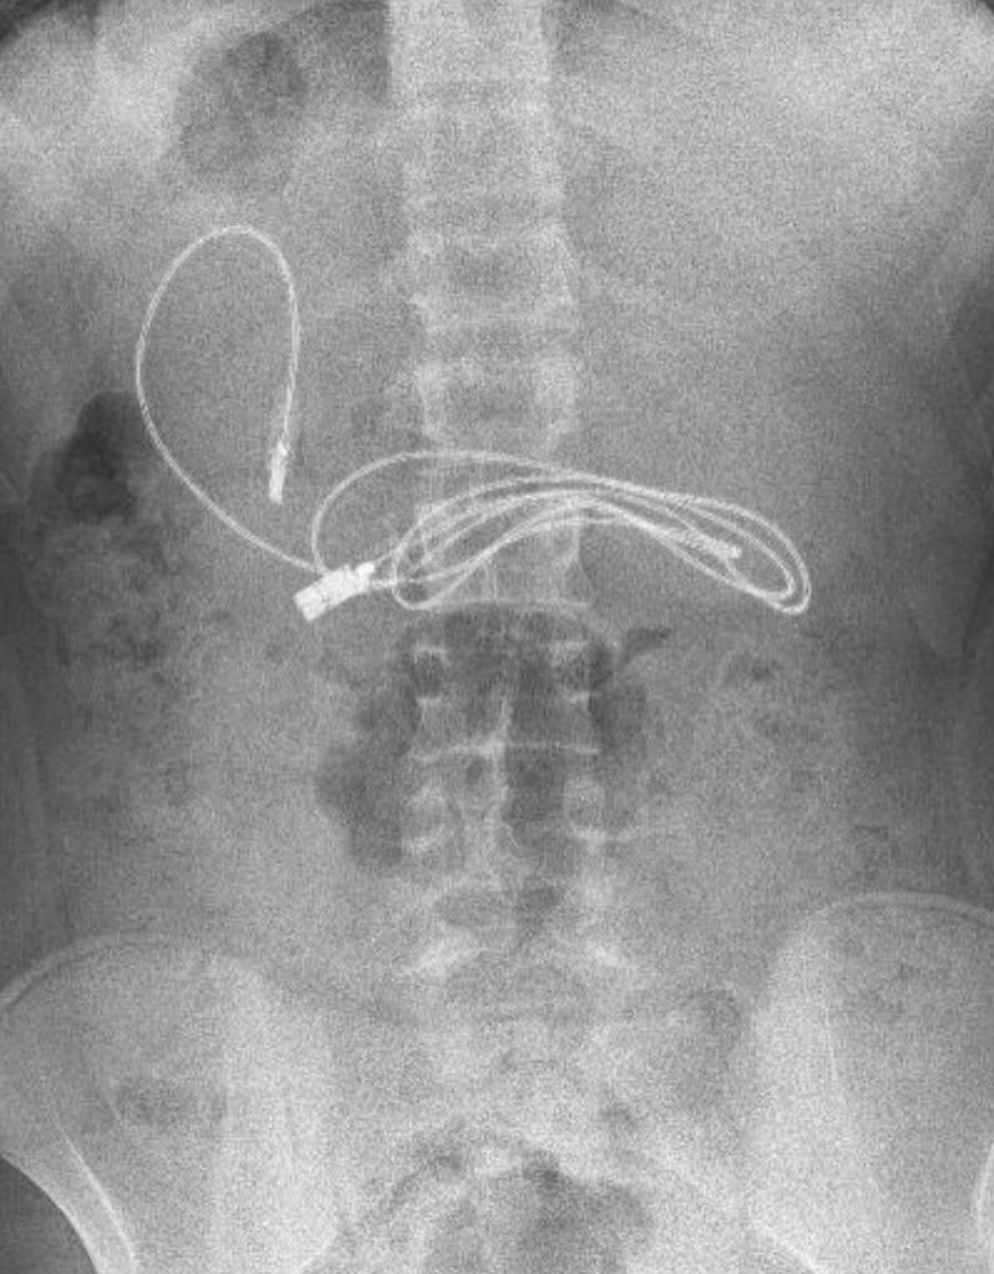

土耳其有一名15歲少年近日不斷感到腸胃疼痛、噁心想吐,於是父母趕忙帶他前往醫院檢查,沒想到經X光檢查後,醫生竟發現少年的胃裡卡著一條100厘米長的充電線,另外還有1條髮圈,讓在場的醫護人員感到相當困惑。

據外媒《紐約郵報》報導,該名少年在出現胃痛及嘔吐的症狀後,被家人送往迪亞巴克爾(Diyarbakir)一家醫院檢查,然而醫生在做完X光檢查後,竟發現少年的肚子裡有一根3英尺(約1公尺/100厘米)長、已纏繞成一團的充電線,還有一條髮圈。

多根教授與其團隊先為少年進行內視鏡檢查後,再以手術從他的胃部取出充電線。多根教授坦言,這場手術相當困難,因為充電線的一端已進入了少年的小腸,而且他的胃部裡還有一根髮圈,醫療團隊必須先用內視鏡檢查再動刀,所幸最終手術順利完成。